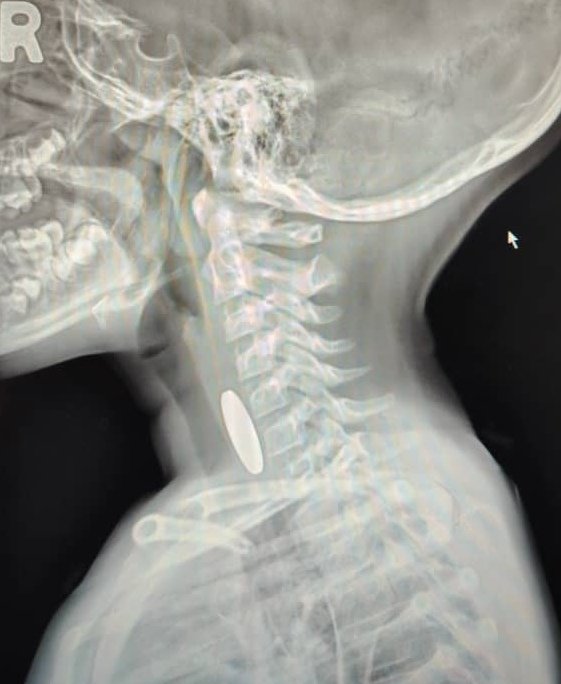

He initially assumed it was a swallowed coin as an X-ray showed a coin-shaped object lodged in the child’s oesophagus.